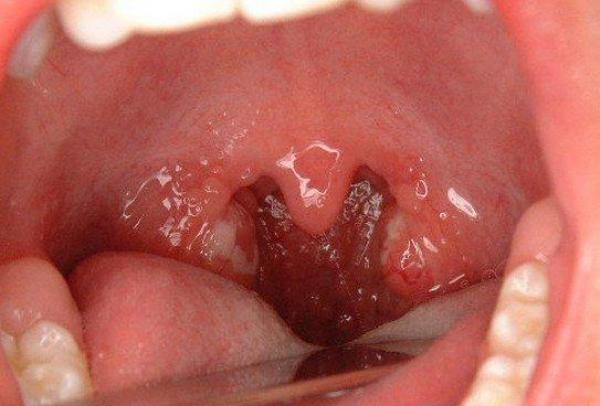

扁桃體發炎是扁桃體的炎症。

臨床上分為急性和慢性兩種,主要症狀是咽痛、發熱及咽部不適感等。

此病可引起耳、鼻以及心、腎、關節等局部或全身的併發症,故應予重視。

扁桃體炎的致病原以溶血性鏈球菌為主,其他如葡萄球菌、肺炎球菌、流感桿菌以及病毒等也可引起。